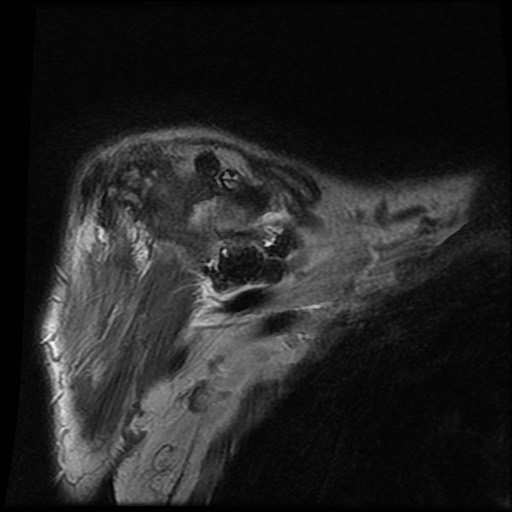

Hình ảnh MRI:

Tràn dịch lan tỏa tất cả các khớp cổ tay.

Phù tủy xương lan tỏa tất cả các xương cổ tay.

Bào mòn xương, ví dụ tại xương thuyền, xương đầu và xương móc.

Phá hủy khe khớp và sụn khớp, rõ nhất tại khớp STT và CMC4/5.